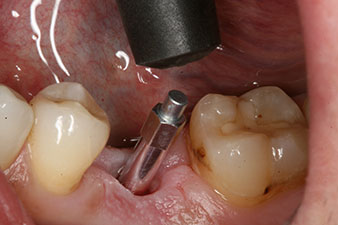

Implantat

Fig. 3: After preparation with the Implantmed implantology motor, an implant (diameter 4 mm, length 12 mm) was screwed in by the motor at a torque of 43 Ncm.

The implant was placed as planned after thorough removal of the granulation tissue (blueSky, bredent).

SmartPeg

Fig. 4: SmartPeg measuring posts screwed on to measure the implant stability quotients with the integrated W&H Osstell ISQ module.

The torque used for the machine-driven placement was 43 Ncm. In addition, after screwing a measuring post (SmartPeg) specially matched to the implant, the ISQ value was measured with the probe of the W&H Osstell ISQ module.